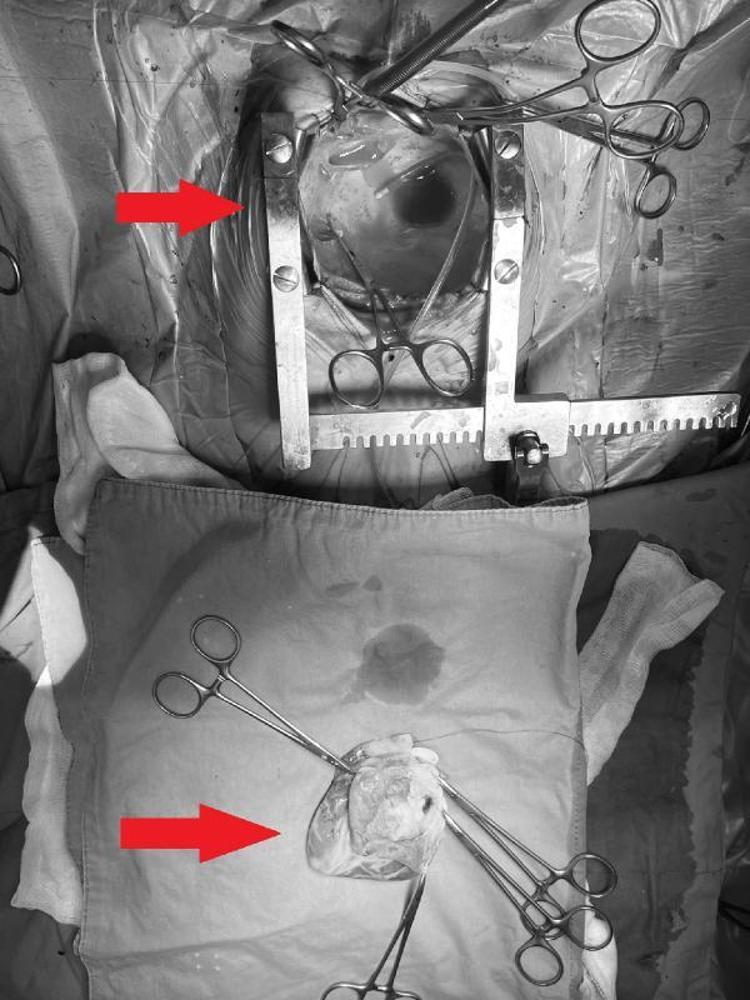

Ekin Ada, geçtiğimiz Ekim ayında Koç Üniversitesi Hastanesi'nde yapılan ve dünya tıp literatürüne girecek bir ameliyatla yeniden doğdu. 8 saat süren ameliyat sırasında Ekin Ada'nın kalbini "yerinden söküp" tümörü ameliyat masasında temizledikten sonra tekrar nakleden, “yüzyılın kalp cerrahları" arasında anılan Prof. Dr. Afksendiyos Kalangos ve Opr. Dr. Yılmaz Zorman, bu eşi benzeri olmayan operasyonu, "O kadar riskli bir ameliyattı ki nefesimizi tutarak yaptık. Kadavradan kalp nakli olsa, elinizde sağlam başka bir organ var. Oto-transplantasyon, yani hastanın kendinden nakilde ise en ufak bir hatada tekrar yerine takabileceğiniz başka bir organ yok" şeklinde anlattı.

Tümörün içinden hayati bir damarın geçmesi nedeniyle kalp yerindeyken ameliyat etmenin imkansız olduğunu anlatan Prof. Dr. Kalangos, çok büyük bir riske girerek kalbi yerinden çıkarıp ameliyat etme yolunu seçtiklerini vurguladı. Prof. Dr. Kalangos, “Çok dikkatli çalışmamız gerekiyordu o nedenle kalbi yerinden söktük, damarlarından ayırdık ve masanın üzerine yatırarak (kalp vücuttan ayrıyken) ameliyata devam ettik. Göğüs boşluğu tamamıyla boş kaldı, 'kalpsiz' bir durumda makineye bağlı takip edildi. Kalbi masanın üzerinde sol karıncığa hasar vermeden, hem kasları hem arterleri koruyarak açtık. Dr. Yılmaz Zorman ile beraber nefesimizi tuttuk, ince ince, soğan kabuğu soyar gibi kalp kasından tümörü ayırdık. Tümörün içinden geçen o ince, bir milimetrelik koroner damarı bulduk ve onu da titiz bir şekilde tümörden ayırarak kalbi tamamen temizledik. Onarılmış kalbi tekrar yerine taktık" dedi.